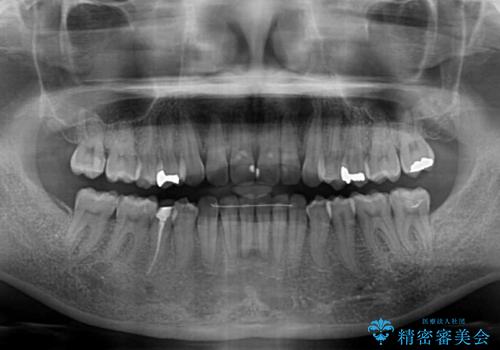

- 前歯のデコボコを気にして来院された患者様です。

IPR(歯と歯の間を削る)によってデコボコが解消するように設計し、インビザラインにより治療を行うこととしました。

下顎善の叢生をもう少し改善したかったのですが、患者様は十分に整ったとのことで治療を終えることになりました。